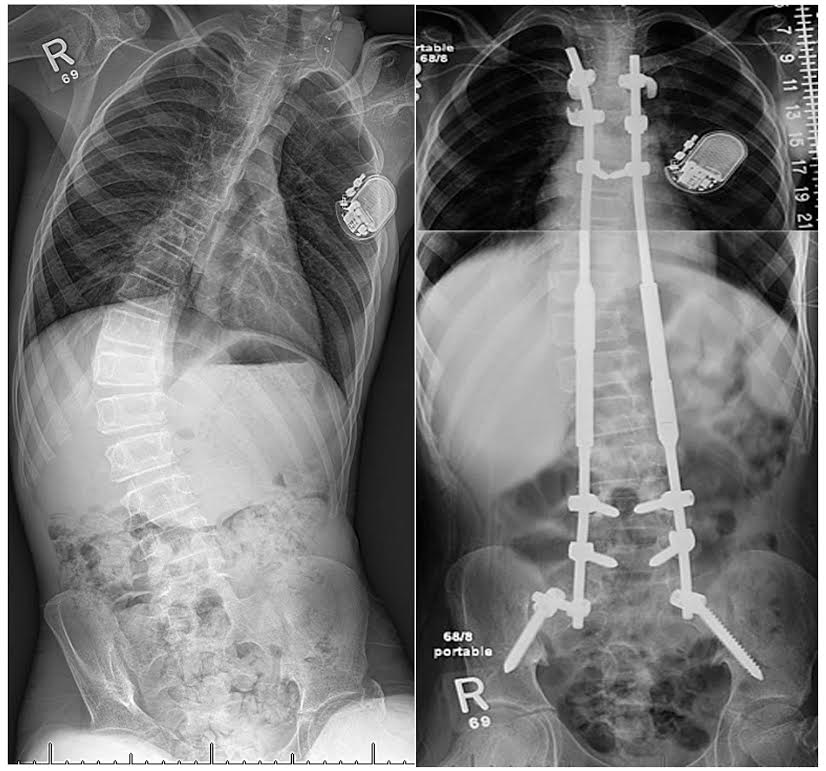

A nine-year-old Emirati girl received a revolutionary new magnetic rod treatment for scoliosis in Abu Dhabi, after her parents brought her back from the US where she was receiving care.

The MAGnetic Expansion Control (MAGEC) rod treatment, which, after the first surgery, is a non-invasive method of treating scoliosis using magnets, is a new alternative to painful invasive spinal surgeries according to Dr. Yaqoob al Hammadi, the Chair of the Orthopaedic Department and Deputy Chief Medical Officer at the Abu Dhabi-based Sheikh Khalifa Medical City (SKMC), where the procedure was carried out.

Similar to conventional growing rod treatment, the MAGEC telescopic rods are surgically fixed to the patient's spine in order to brace and straighten it during growth. The difference, however, is one that could save several painful invasive surgeries as the patient grows.